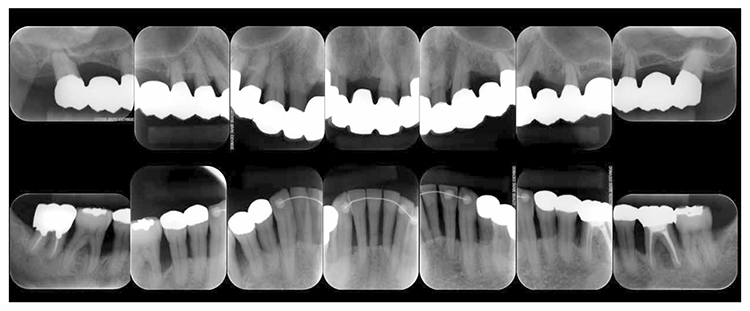

(3) X-ray findings

At the first visit, the findings showed moderate to advanced horizontal alveolar bone resorption in the entire jaw, and advanced vertical bone resorption on 24,36,46, 47. Additionally, on 46,47 were radiolucent findings that were likely associated with furcation involvement, and radiolucent areas on the alveolar bone surrounding the root apex were shown on 16,11,26. Furthermore, distally on 47, radiolucent findings showed caries extending into the dental pulp.(Fig.1c).

Fig 1c

(Fig.1c) Dental X-ray 14 during first visit (June 2007)